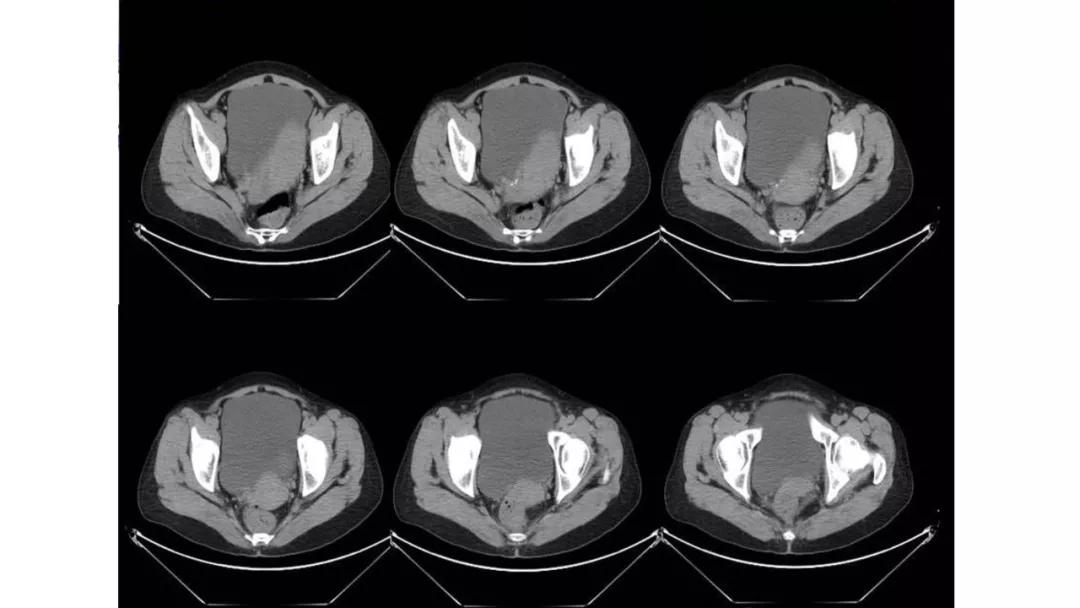

病例10

女,39 岁,体检发现盆腔肿块1月余

CA125:51U/ml

病理:左侧卵巢卵泡膜-纤维瘤